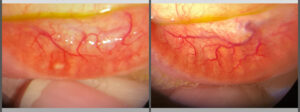

Pushing ahead, our imaging system includes our new, patent-pending Halo background light. Working with native slit lamp illumination, Halo delivers unparalleled clarity of the ocular adnexa. You’ll uncover details of the meibomian glands, acinar spaces, conjunctiva, lid margins, and lashes like never before.